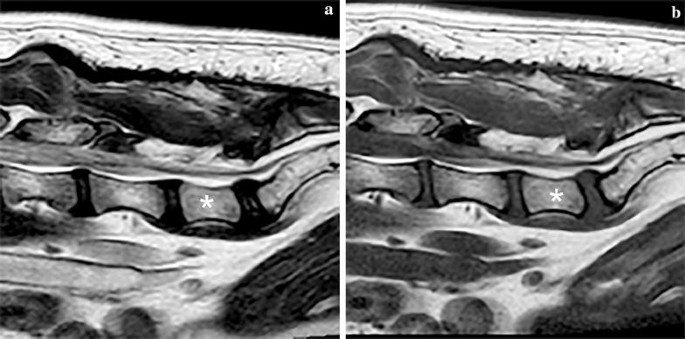

Magnetic resonance imaging was repeated from C1 to S1, including sagittal and transverse T1-weigted and T2-weighted sequences, and a transverse FLAIR sequence of the lumbar spine. Multiple intervertebral discs showed decreased hypointense signal compatible with intervertebral disc degeneration. At the level of C2–C3, T12–T13, T13–L1 and L1–L2 mild disc protrusion was found with visible compression of the ventral subarachnoid space, but without compression or dislocation of the spinal cord. A fusiform cystic lesion dorsal to the cauda equina at the level of L6–L7 was found with an ill-defined cranial and caudal border. The cystic structure was isointense to CSF and compressed the cauda equina (Fig. 5). Based on these imaging characteristics a SAD was suspected. There was mild dilation of the central canal from T12 to L5.

Magnetic resonance images of the caudal lumbar vertebral column of Case 2, including T2-weighted sagittal (a), T1-weighted sagittal (b), T2-weighted transverse (c), and FLAIR transverse (d) images. The subarachnoid diverticula is marked with an arrow on all images and L7 is labelled with an asterisk on images (a) and (b)